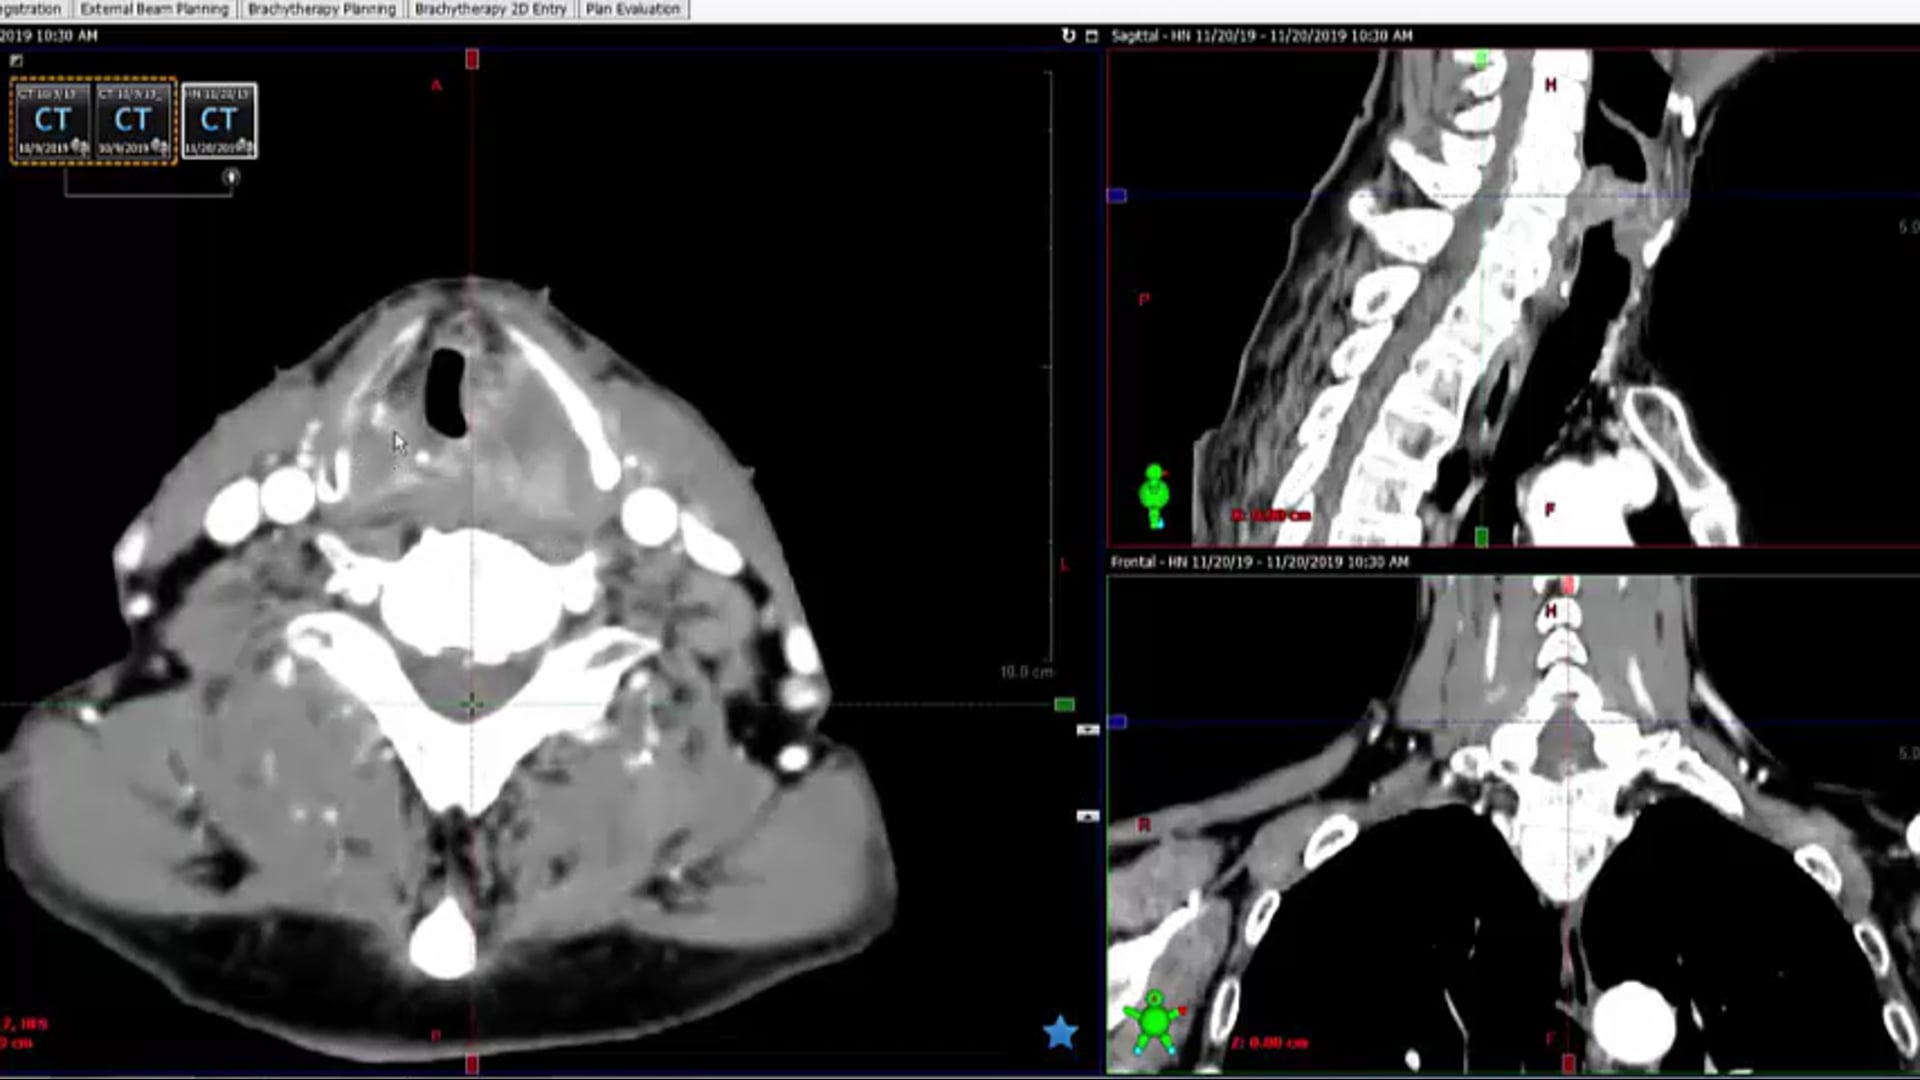

12/10/19 - Dr. Kenneth Hu - Radiation Oncology - Head and Neck US

-